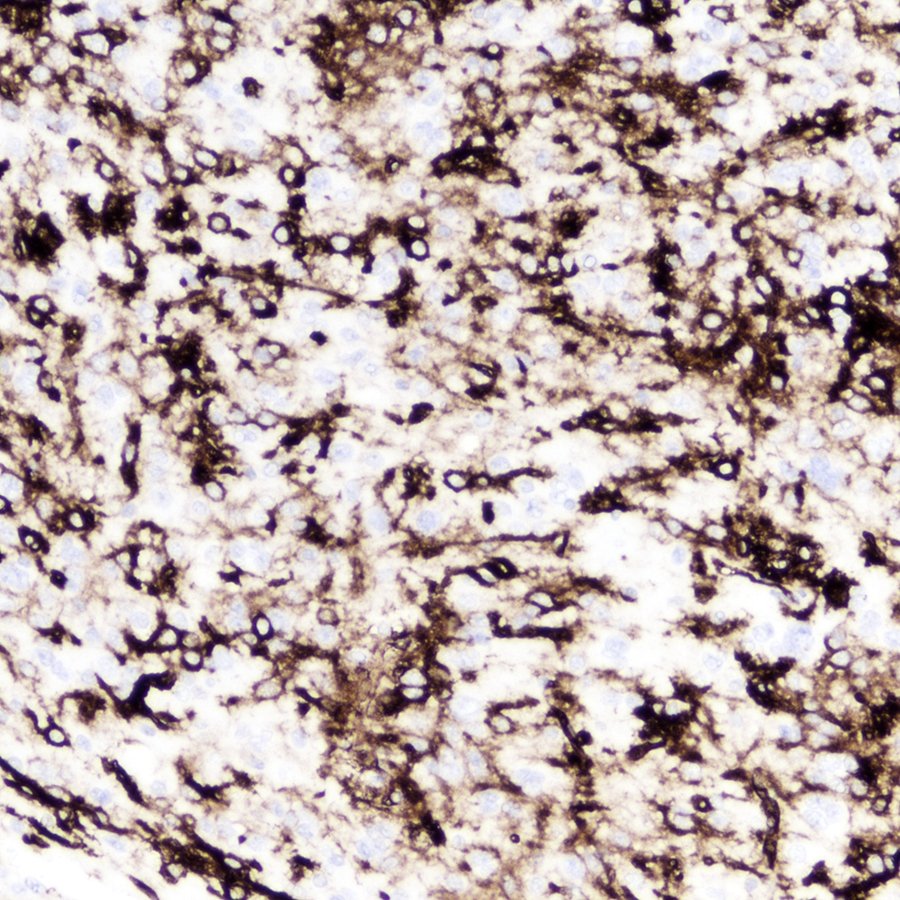

Superficial well-circumscribed temporal lobe mass in a young woman. NGS showed a BRAF V600E mutation. Diagnosis? (The CD34 immunostain at the end is PLeNTY good enough.) #pathology #neuropath #PathTwitter